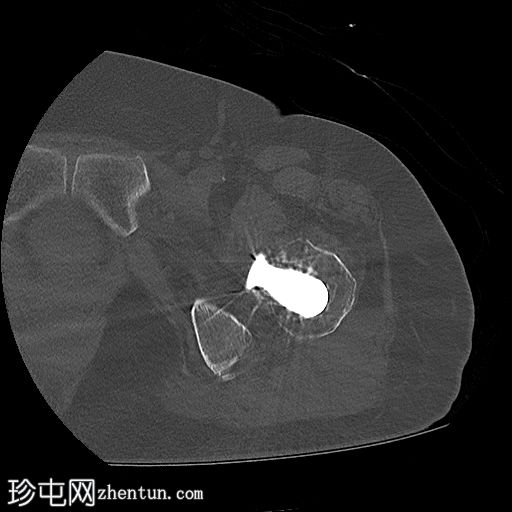

轴位骨窗

左侧全髋关节置换术。大转子基底部可见轻微移位的假体周围骨折。

大转子滑囊积液,可见脂肪-液体平面。